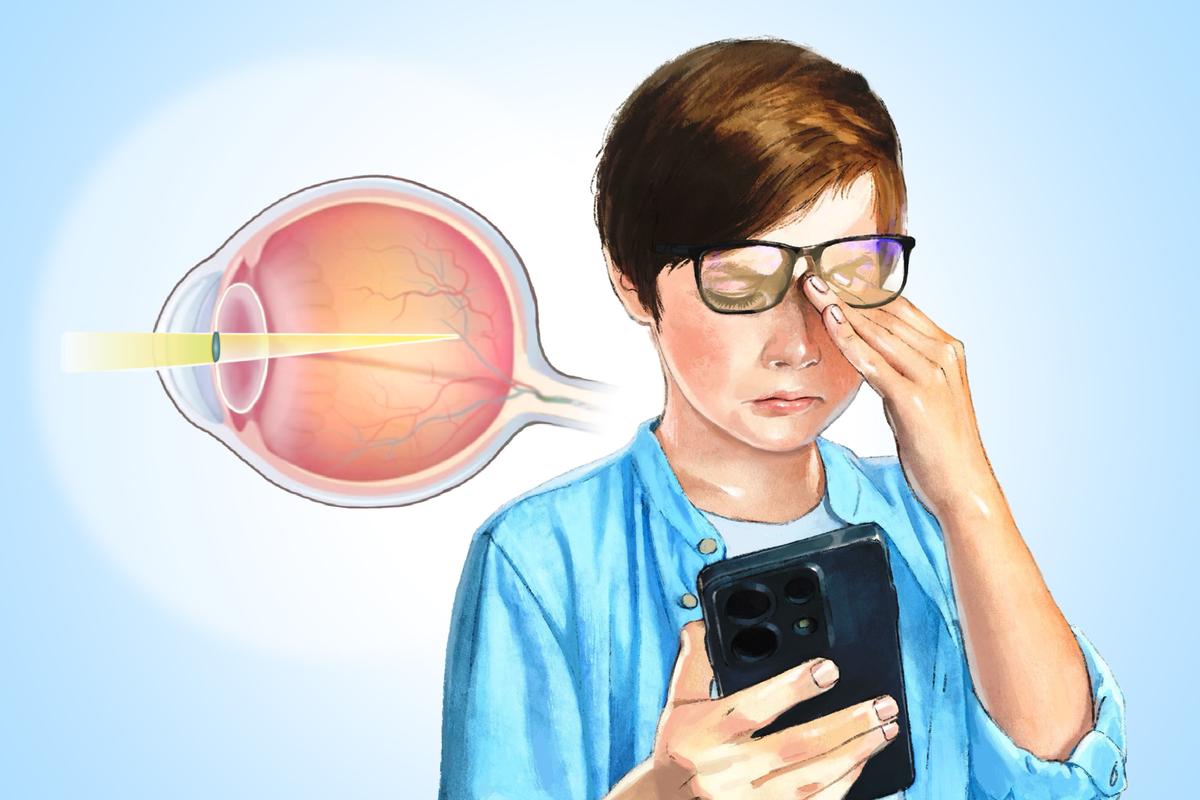

Myopia: 2 in 5 People Are Affected–Here’s How to Slow Progression

A 2020 study found the average progression rate was -0.40 diopters per year in children whose myopia progressed.

Myopia: 2 in 5 People Are Affected–Here’s How to Slow Progression

A 2020 study found the average progression rate was -0.40 diopters per year in children whose myopia progressed.

Myopia: 2 in 5 People Are Affected–Here’s How to Slow Progression

A 2020 study found the average progression rate was -0.40 diopters per year in children whose myopia progressed.